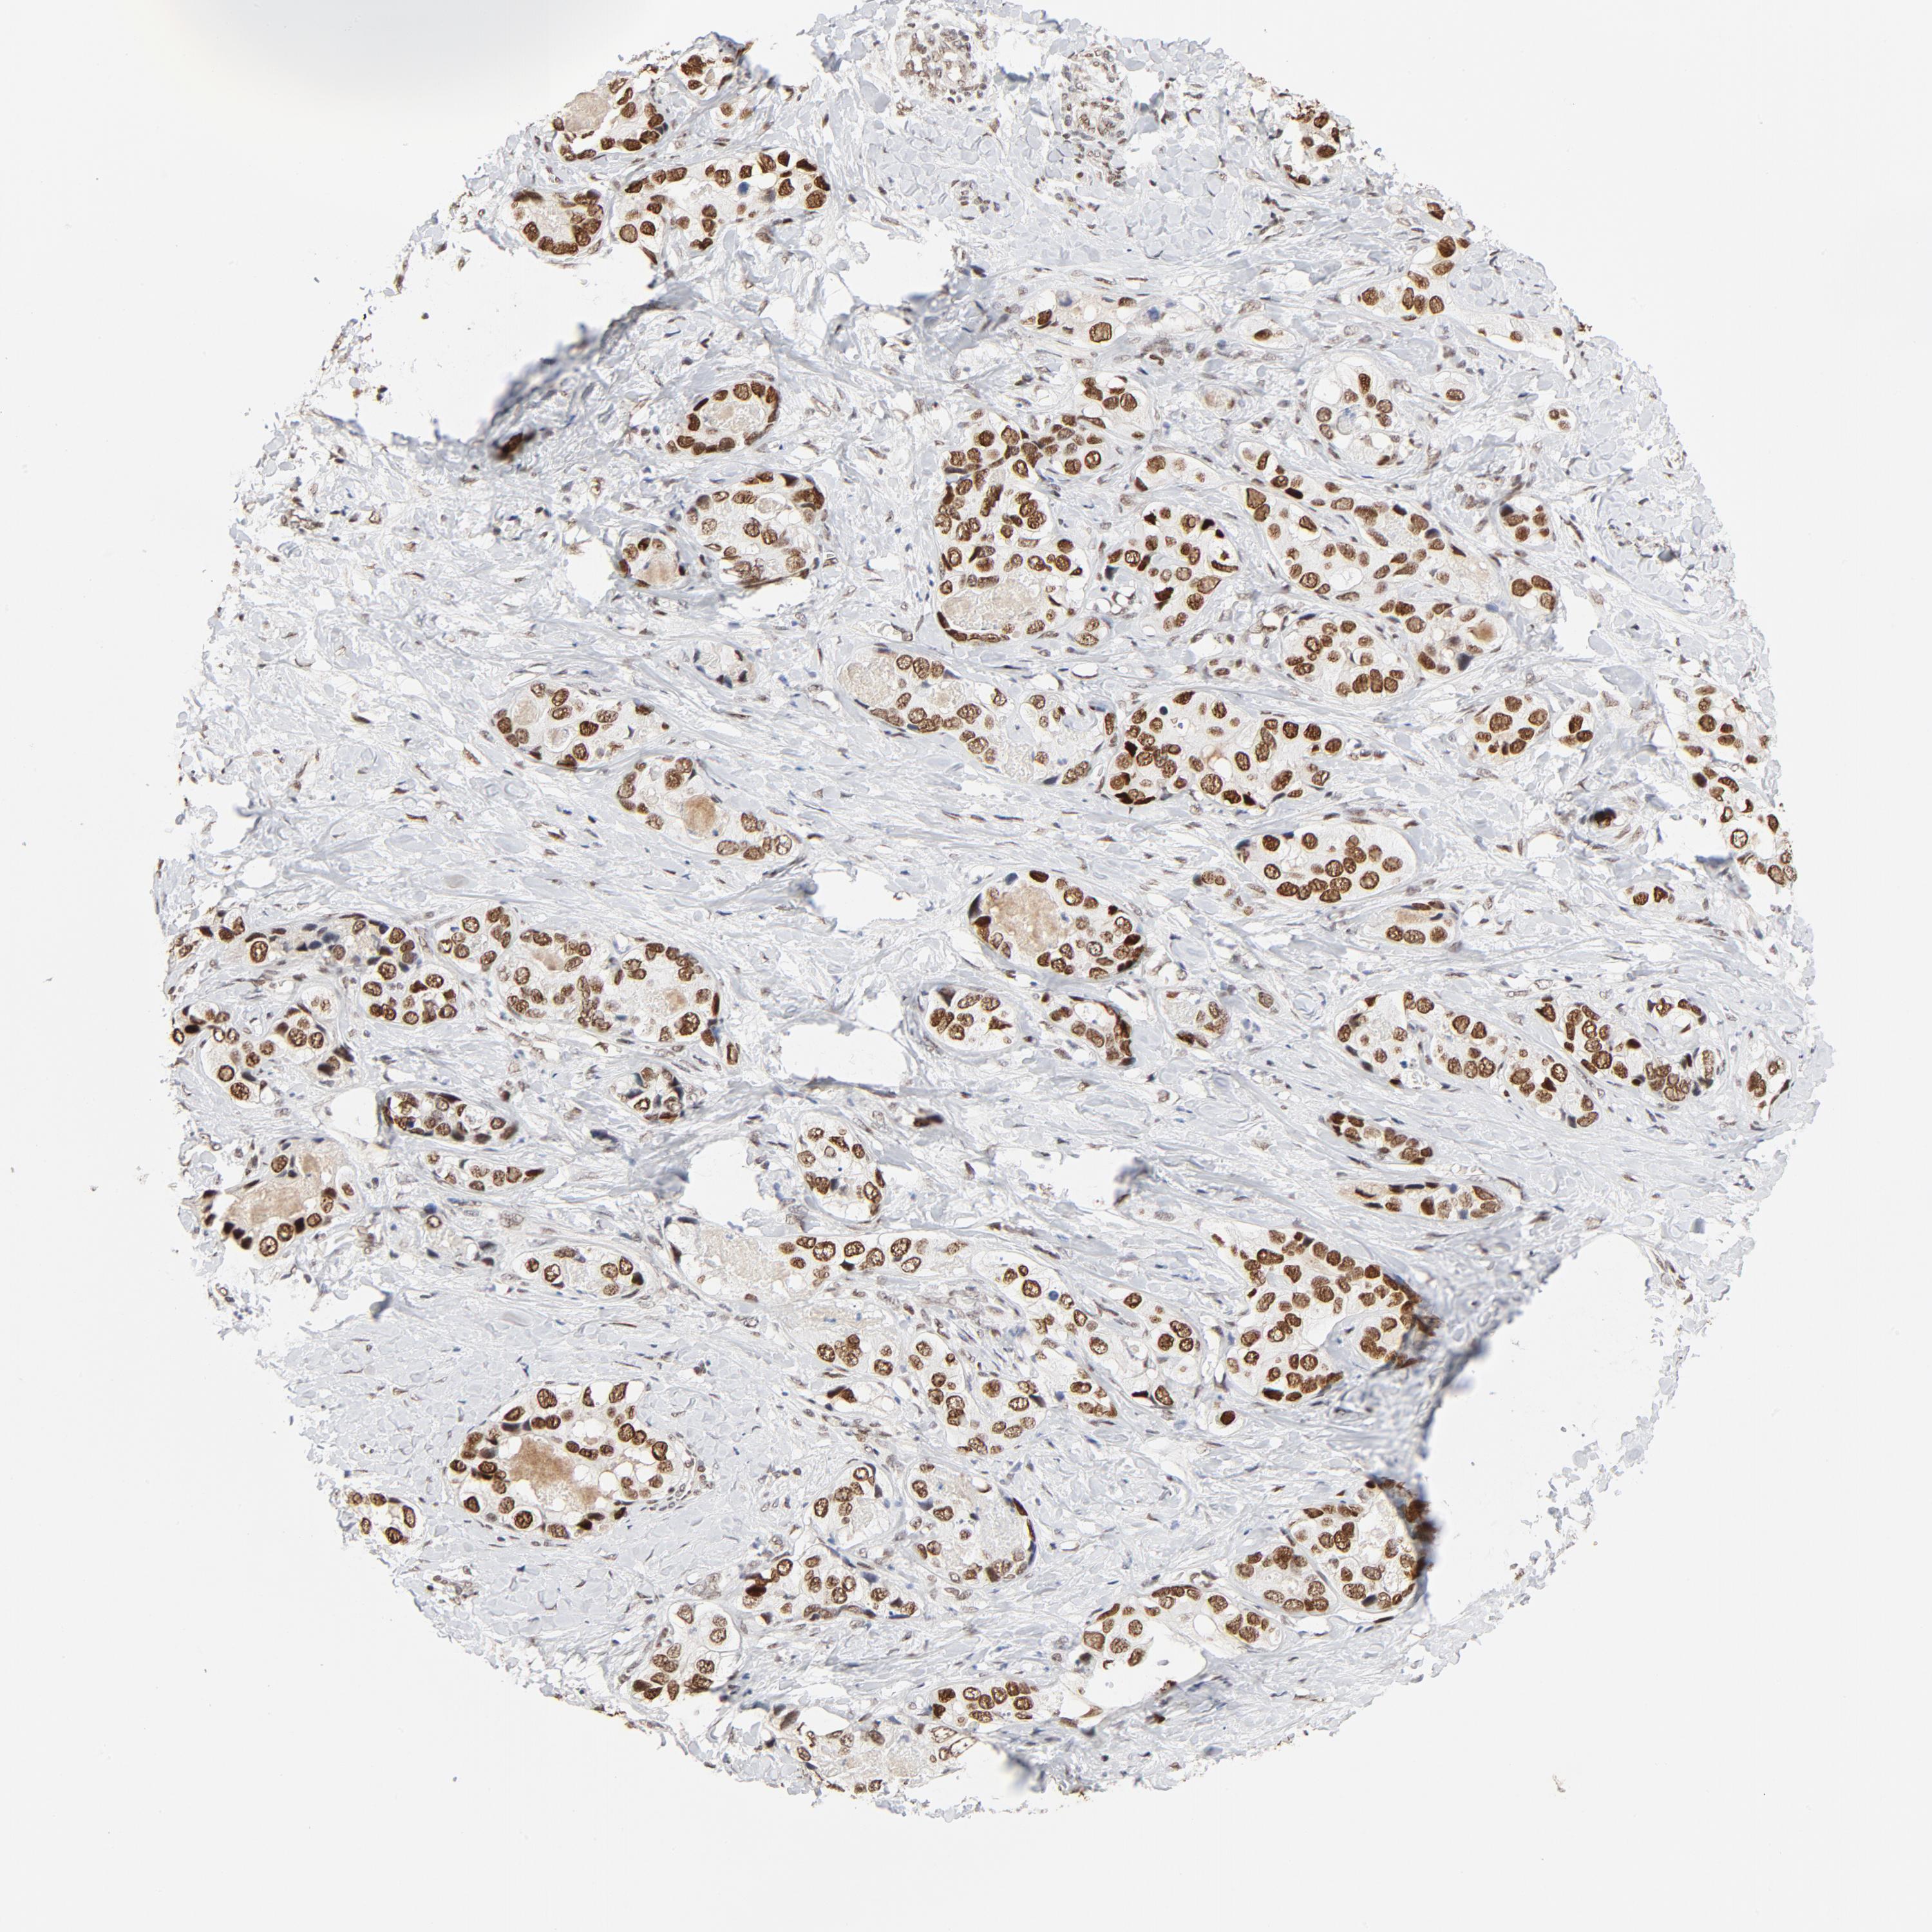

LIVER CANCER - Protein expressioni

A mouse-over function shows sample information and annotation data. Click on an image to view it in a full screen mode. Samples can be filtered based on level of antibody staining by selecting one or several of the following categories: high, medium, low and not detected. The assay and annotation is described here.

Note that samples used for immunohistochemistry by the Human Protein Atlas do not correspond to samples in the TCGA dataset.

Antibody stainingi

Antibody staining in the annotated cell types in the current human tissue is reported as not detected, low, medium, or high, based on conventional immunohistochemistry profiling in selected tissues. This score is based on the combination of the staining intensity and fraction of stained cells.

Each image is clickable and will lead to virtual microscopy that enables deeper exploration of all samples and also displays staining intensity scores, fraction scores and subcellular localization as well as patient and tissue information for each sample.

Antibody HPA026638

Antibody CAB004595

Staining

High

Medium

Low

Not detected

Intensity

Strong

Moderate

Weak

Negative

Quantity

>75%

75%-25%

<25%

None

Location

Nuclear

Cytoplasmic/membranous

Cytoplasmic/membranous,nuclear

Cholangiocarcinoma

Carcinoma, Hepatocellular, NOS